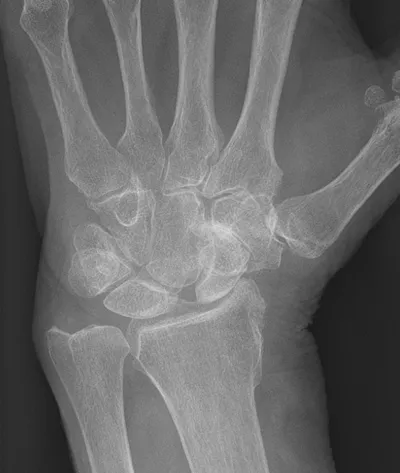

4-Corner carpal fusion of wrist

XRAYHandCarpal+2